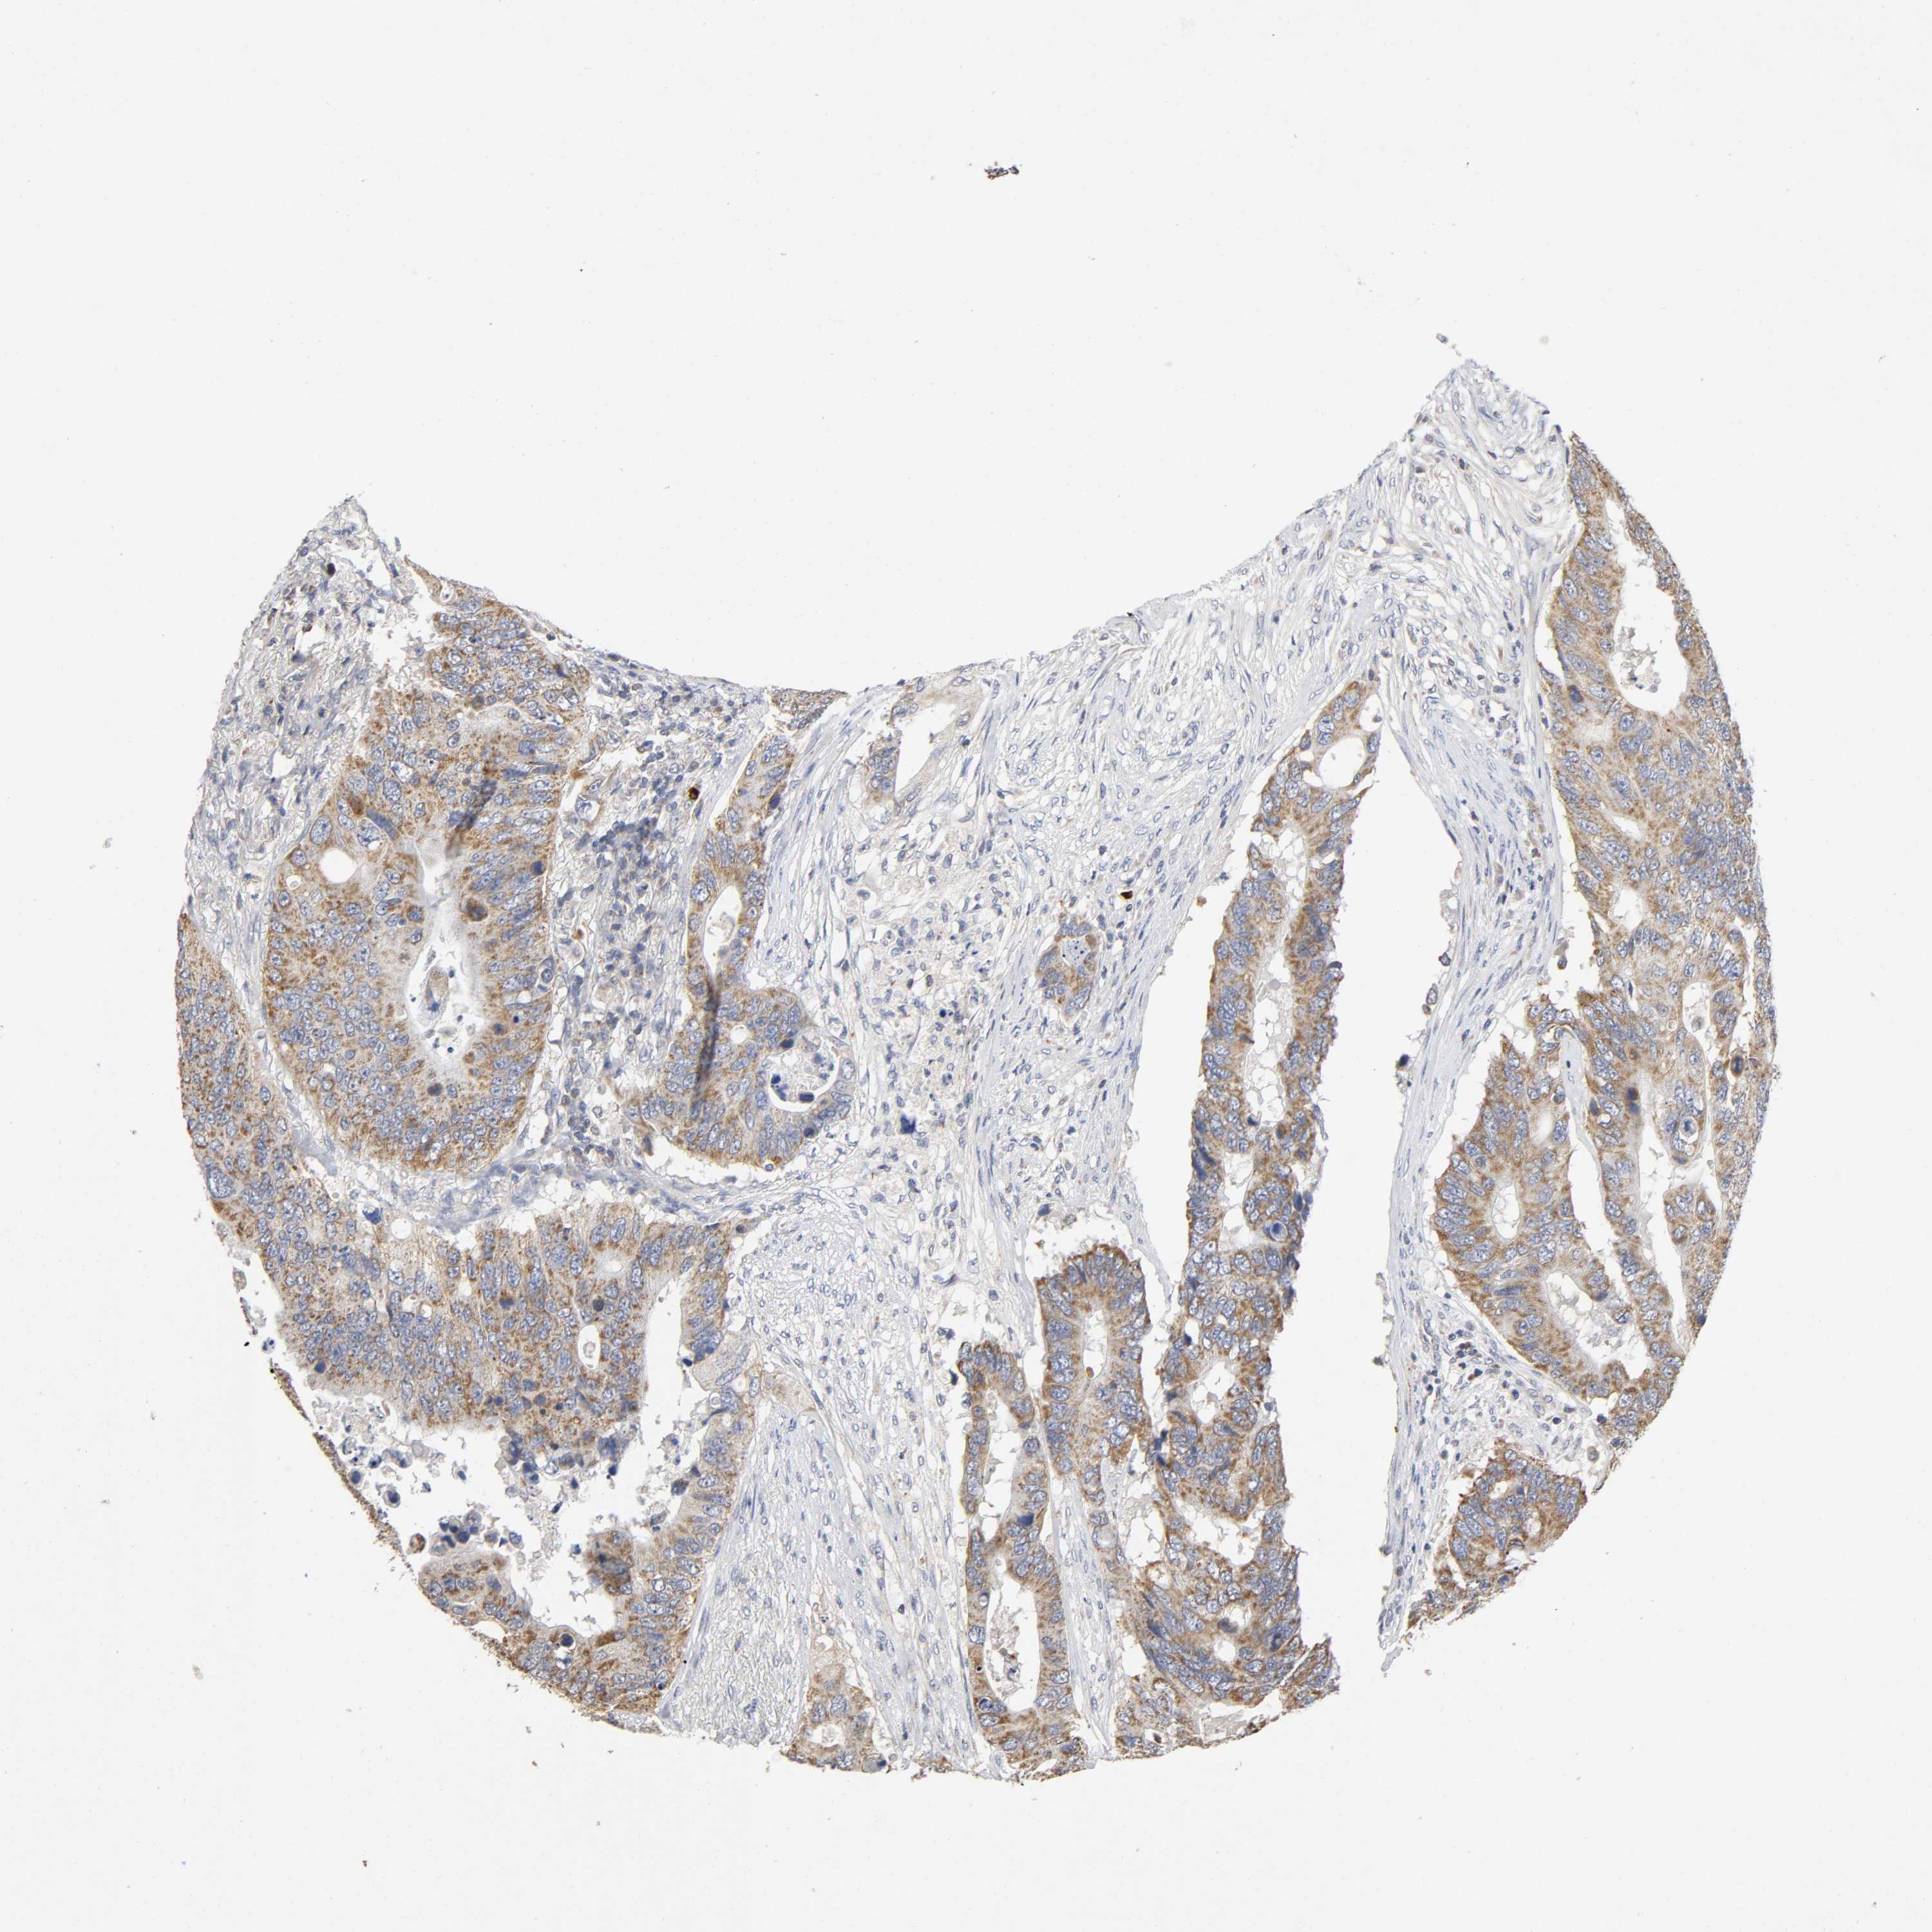

CANCER COLORECTAL CANCER Show tissue menu

Colorectal cancer

Human cancer

Colon adenocarcinoma